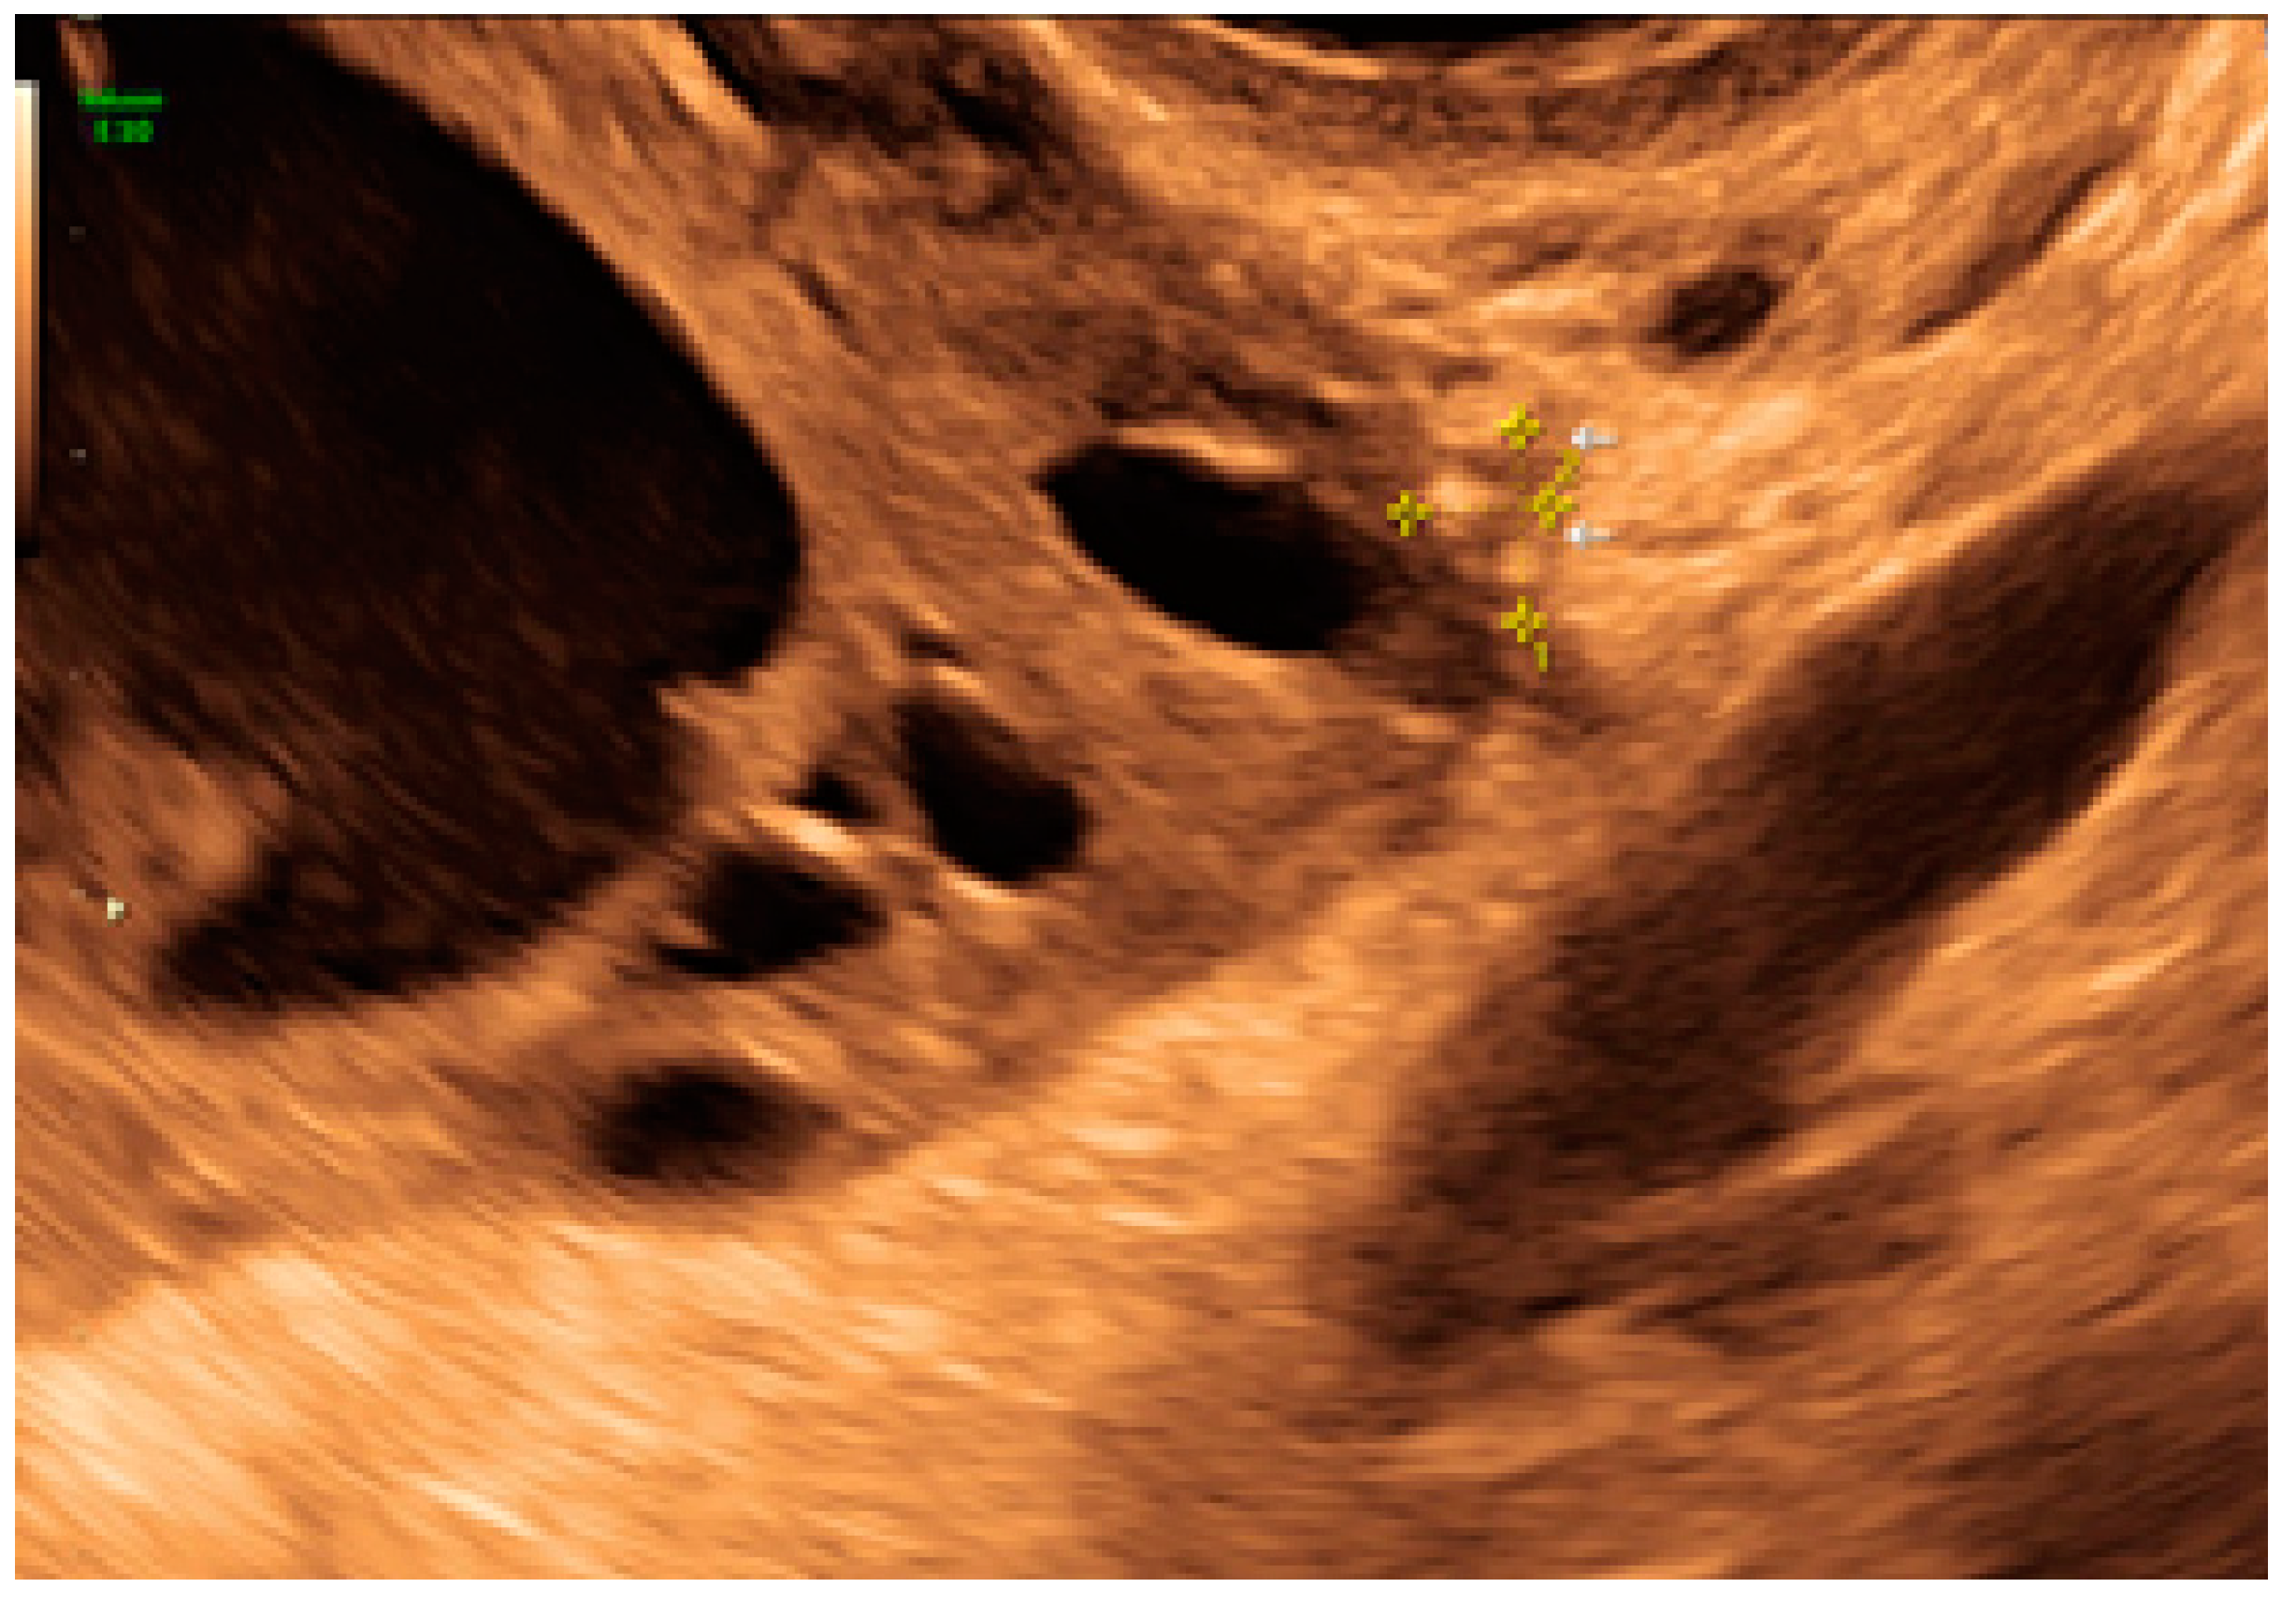

- The presence of hyperechoic foci (we called this a “pearl”).

- The presence of velamentous (filmy) adhesions associated to the lesion (we called this a “veil”).